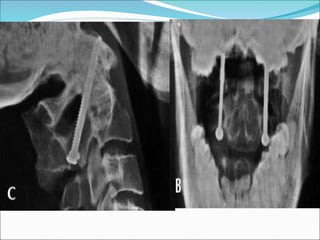

FRATURAS DO PROCESSO ODONTÓIDE

 Técnicas de tto:

 Imobilização com Halo-gesso por 12 semanas

 Fixação com parafuso intrafragmentar

 Artrodese posterior C1-C2

 Osteossíntese pela via anterior (mais anatômica)

 - não indicada nas fraturas irredutíveis por métodos

fechados e lesões crônicas

 - idosos com osteoporose e fraturas patológicas tb é

contraindicada

 No intuito de guiar a indicação da técnica, Grauer:

 IIA: fratura sem desvio

 IIB: fratura com desvio que corre de anterossuperior

para posterosuperior ou uma fratura transversa

(favorável a via anterior)

 IIC: anteroinferior para posterossuperior ou que

apresenta cominuição significativa -> não pode ser

tratada satisfatoriamente com osteossíntese